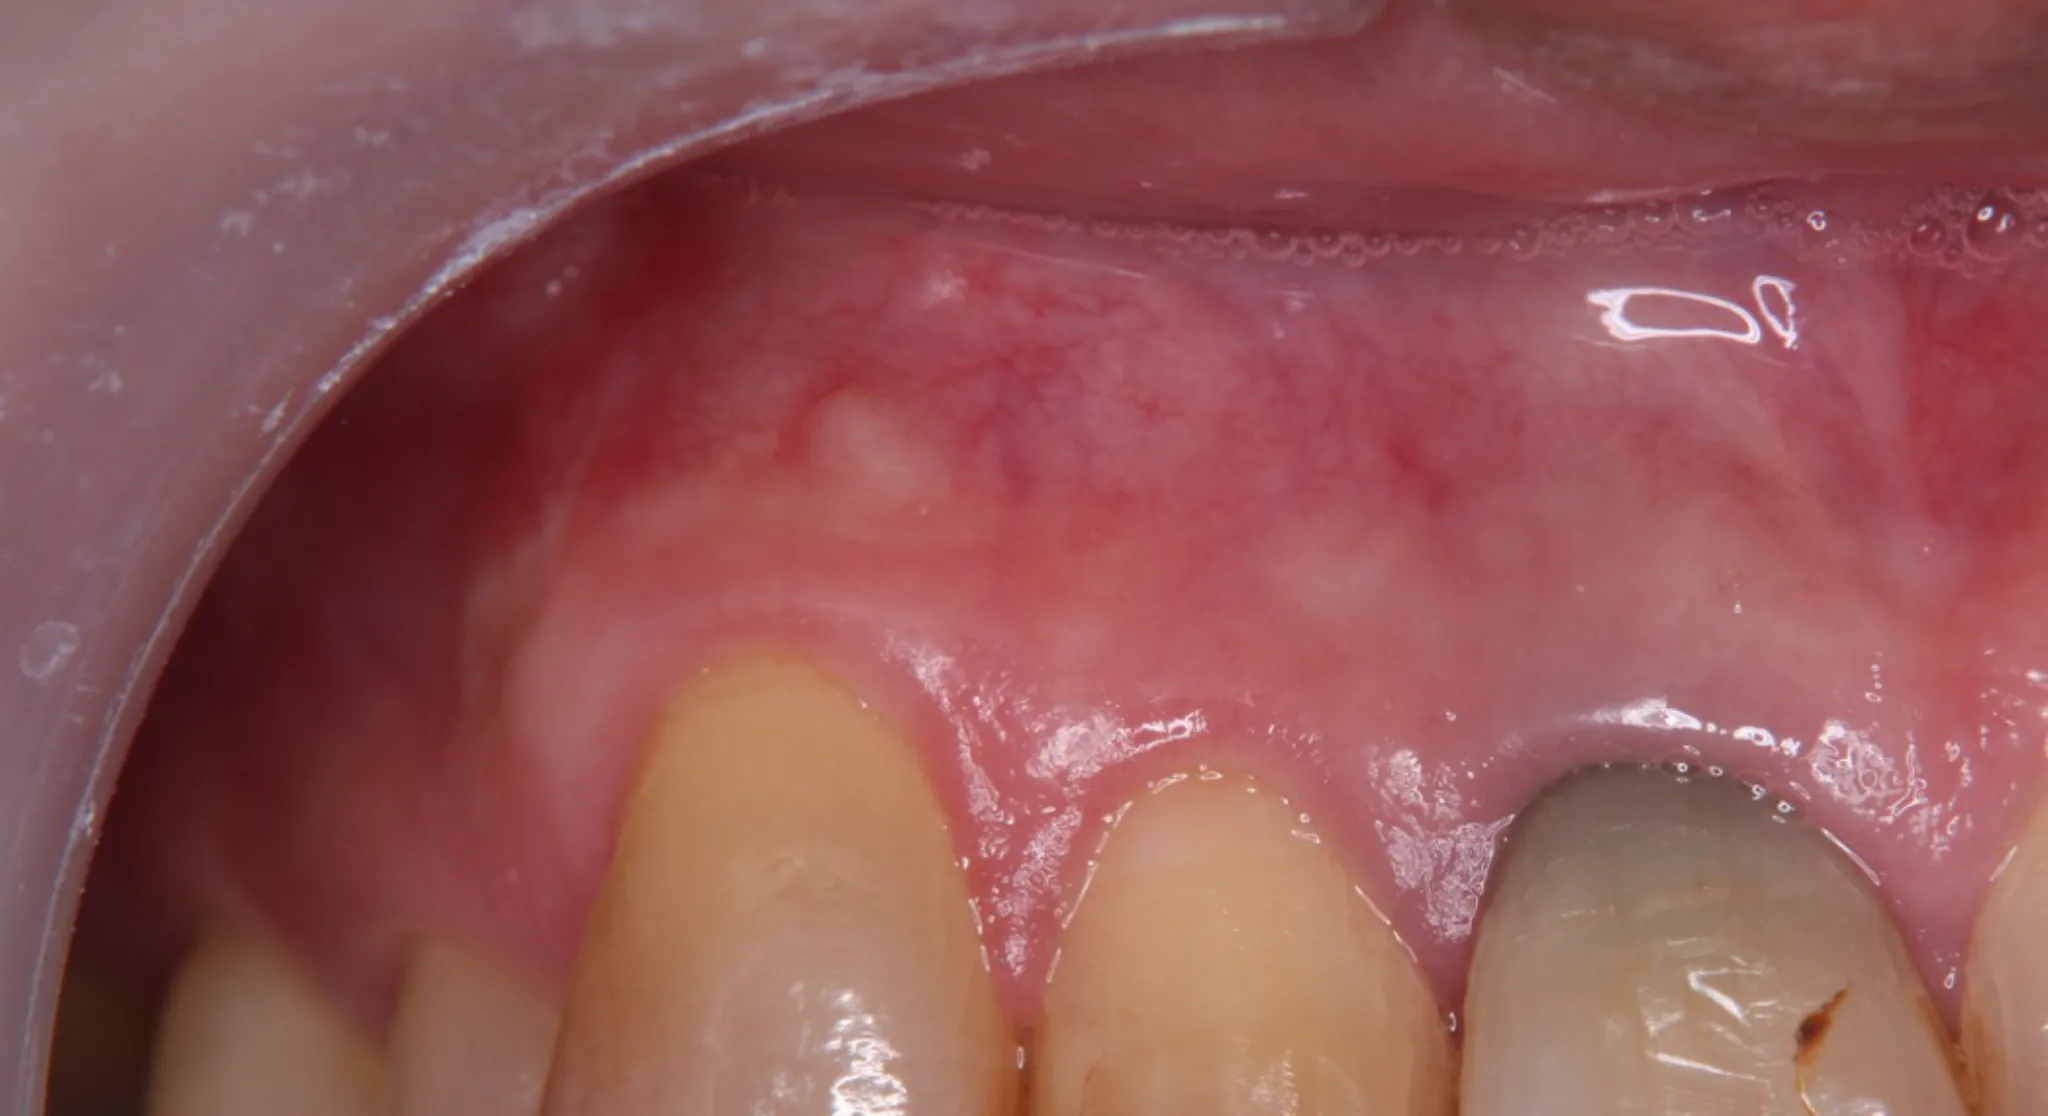

当院では、最新の技術を積極的に導入し、精度の高い治療を提供しています。

特に、すべての治療においてマイクロスコープを導入することで精密な治療を実現します。

最新技術の導入により治療の精度が向上し、再発のリスクを減らすことができるため、患者さんにとっての長期的な健康を守る重要な手段となっています。 -